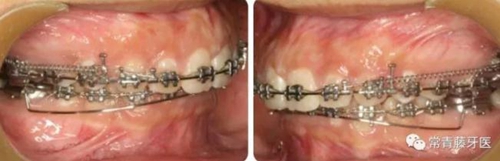

A67、B67之間植入微種植釘整體內(nèi)收上牙列,下頜配合多用途弓整平牙列改善覆合。

繼續(xù)內(nèi)收上牙列,此時(shí)下頜spee曲線基本整平。